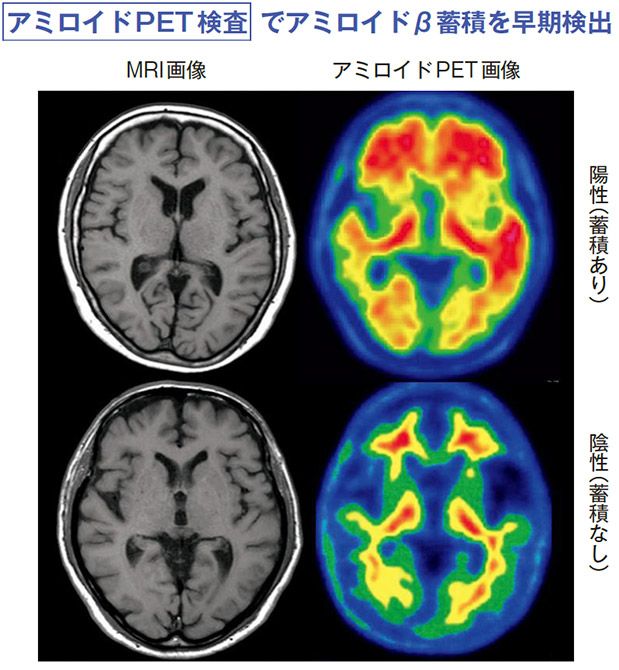

MRI 検査で「異常なし」の判定であってもアミロイドPET を行うとアミロイドβの蓄積が検出されることがある。しかも、蓄積の有無だけでなく、蓄積量と分布も調べることが可能だ。

アミロイドβと結合する放射性薬剤を注射後、アミロイドPET を行い、脳内のアミロイドβの蓄積量と分布を調べる。